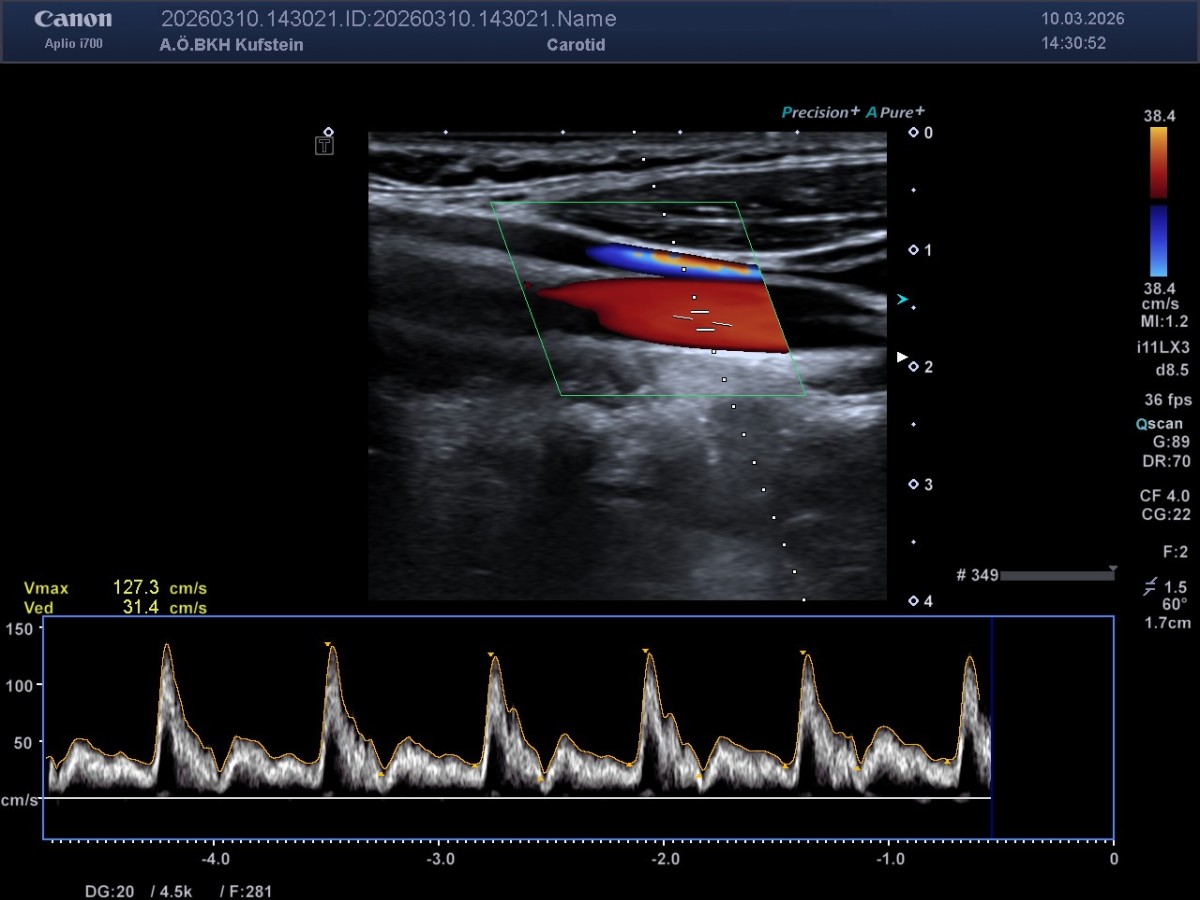

Die MedETeCh Gruppe der diesjährigen siebten Klassen besuchte am 10. März 2026 mit Frau Prof. Mag. Enthofer und Herr Prof. Mag. Dr. Zwicknagl die Abteilung für Radiologie im Krankenhaus Kufstein, um ihr medizinisches Wissen in der Praxis auszutesten. Oberarzt Dr. Martin Neururer, Radiologie-Technologe BSC Robert Nußbaumer und Dr. Paul Peyrer hießen die Schüler*innen in der Radiologie willkommen und unterstützten sie bei ihren ersten Ultraschallversuchen. Nieren, Leber, Milz, Herz, Carotis und Achillessehne konnten von den Schüler*innen eigenständig lokalisiert und anschließend auf dem Bildschirm sichtbar gemacht werden. Die Schüler*innen bedanken sich herzlich beim Team des BKH Kufstein für die freundliche und kompetente Betreuung und die Möglichkeit, selbst aktiv zu werden.